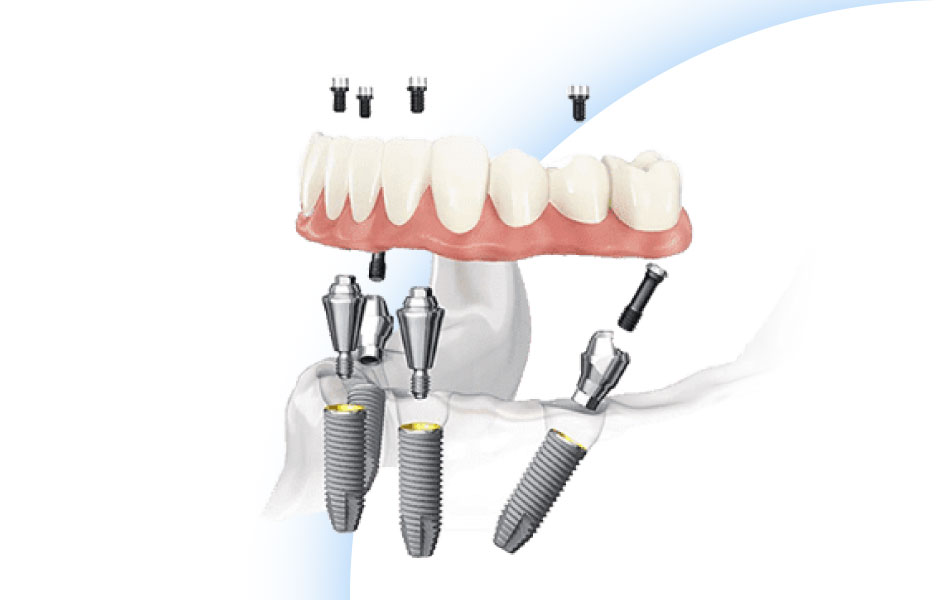

О технологии имплантация зубов All-on-4

Возможность жевать пищу естественным путем, красиво улыбаться и вести социальную жизнь без ограничений поднимает уровень жизни на новую высоту, повышает уверенность в себе и устраняет комплексы из-за плохих зубов. При этом вам не понадобится установка имплантов на все утраченные зубы, как в стандартных технологиях имплантации, а достаточно всего 4 опор, что существенно уменьшает стоимость процедуры и упрощает ее процесс. При частичном отсутствии зубов часто целесообразно удалить оставшиеся неэффективные зубы и применить данную методику.

После качественной подготовки применяется одноэтапный протокол: всего за 1 день в костные ткани устанавливают 4 импланта, а через 2-3 дня - временный несъемный протез из 12 коронок.

Покрытие имплантов и их конструкция отличаются от классических единичных имплантов.

Два искусственных титановых корня вводятся в челюсти прямо, а два других - со стороны жевательных зубов, под углом. Таким образом площадь соприкосновения имплантом с костными тканями больше, и даже при атрофии средней и начальной стадии имплантаты надежно удерживаются в кости, а вся конструкция становится долговечной, устойчивой, прочной.

Несъемный протез получает возможность максимально устойчиво переносить нагрузки с равномерным распределением на каждую единицу. В дальнейшем компания продолжила разработки и усилила эффект для людей с широкой челюстью, добавив в зубные ряды 2 или 4 импланта (методики «Все на 6», «Все на 8»), но основой все рано остается имплантация по протоколу имплантации зубов «All-on-4».